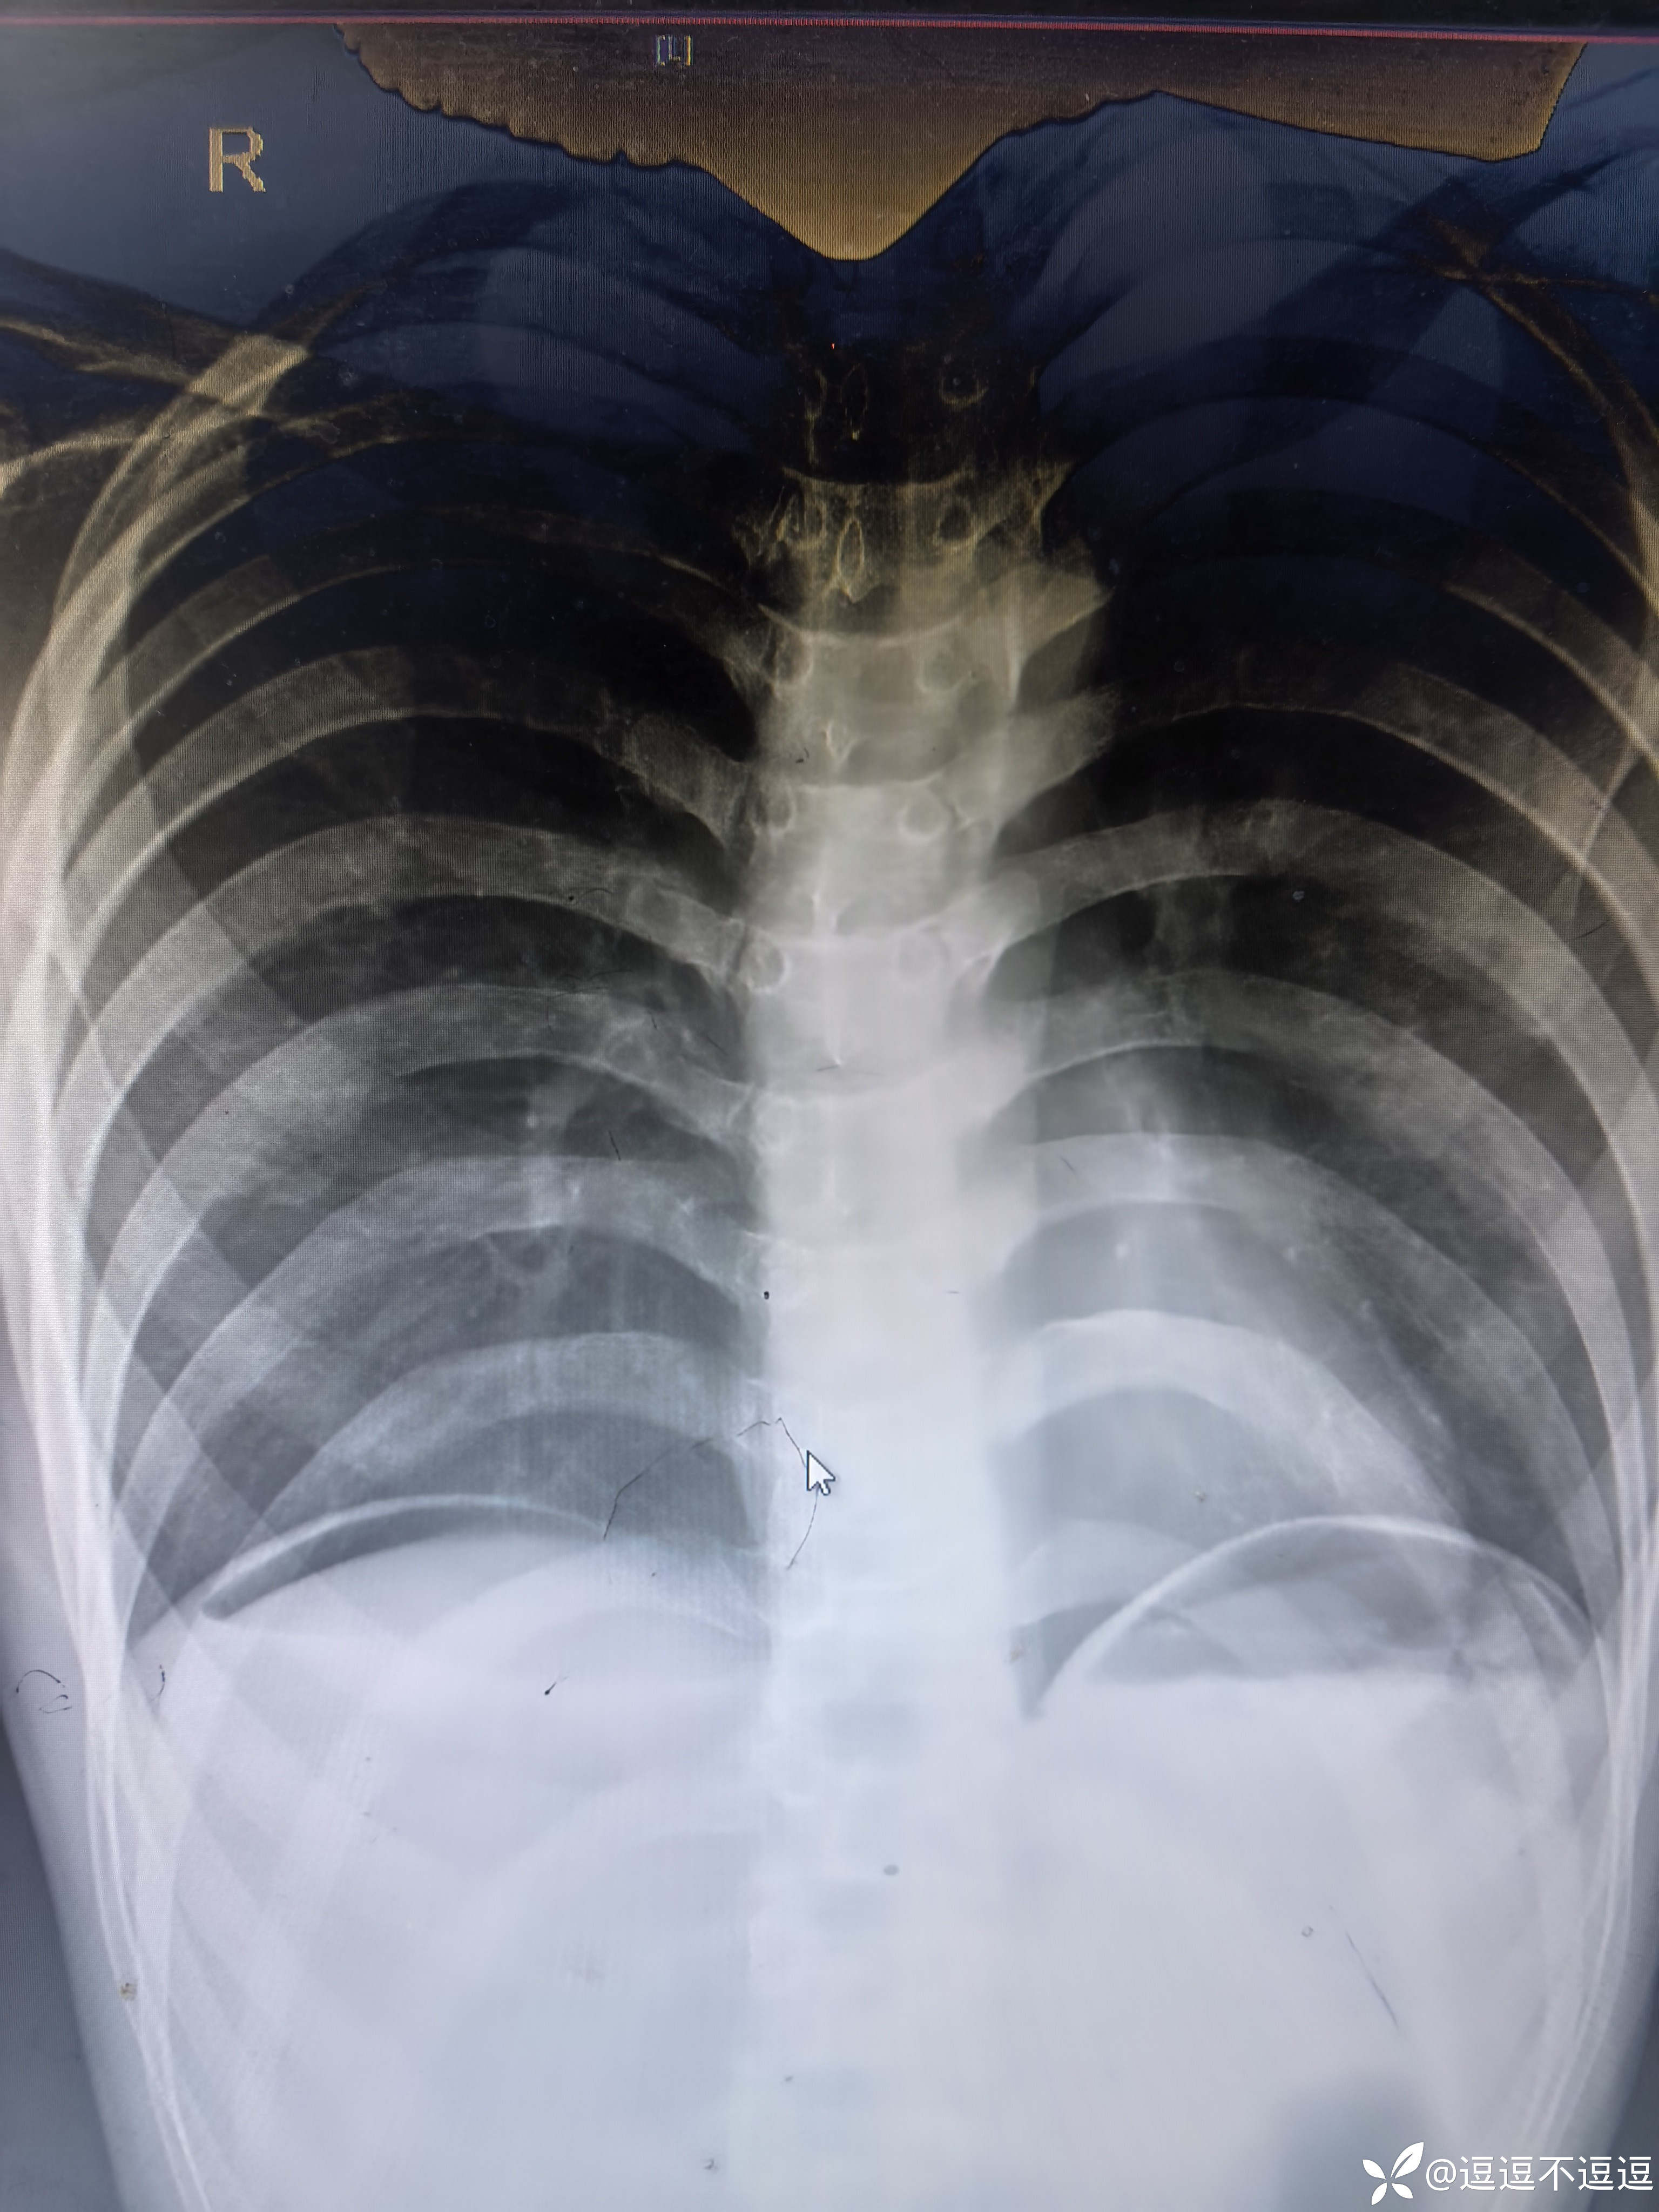

目前患者腹痛加重6小时,结合查体,考虑消化道穿孔,毕竟ct刚做过,那就在做个腹部立位平片

这张膈下新月型的游离气体影很典型

【临床诊断】:①急性弥漫性腹膜炎,②消化道穿孔